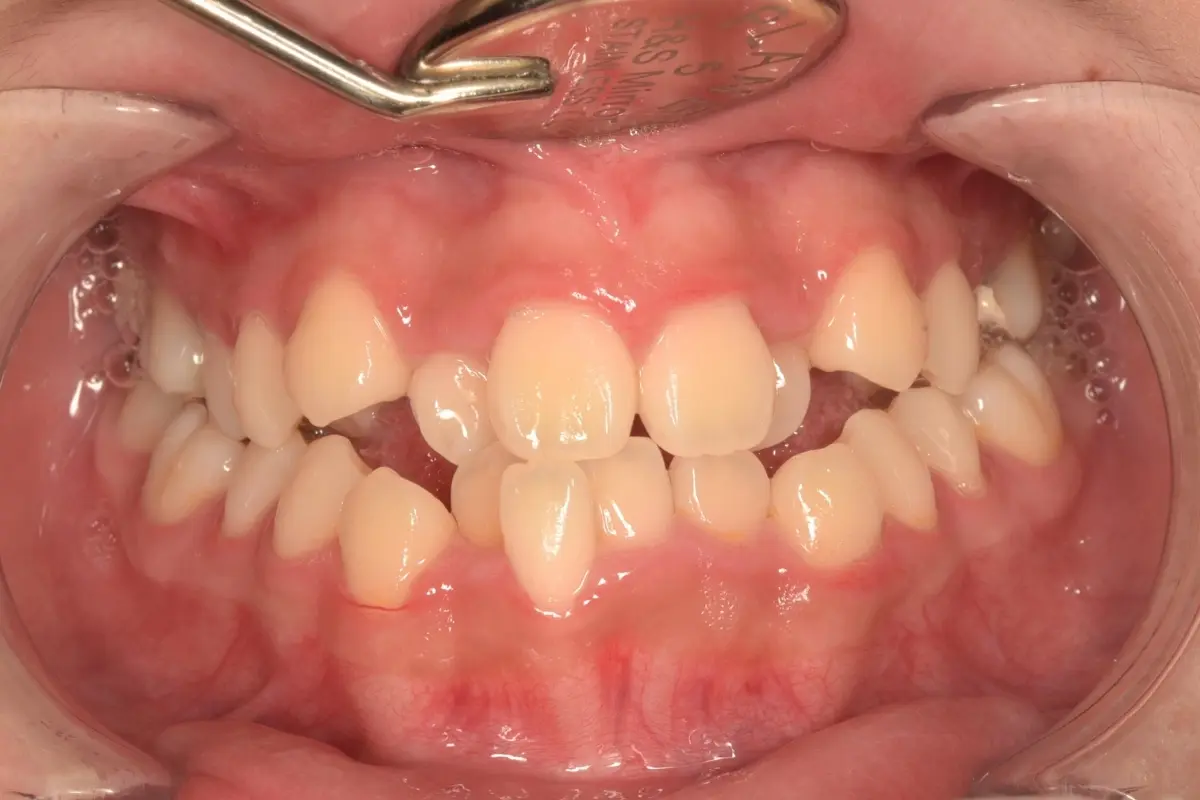

• 術前 44

術後 42

仿生美學樹脂

主治醫師

• 陳暐文

治療時間

單次療程

主訴

門牙有縫、牙齒形狀偏方,笑起來不夠自然